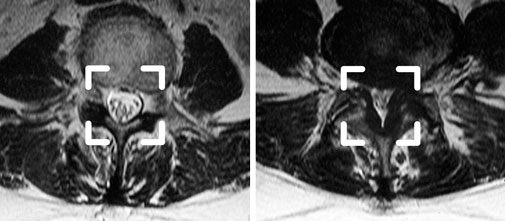

Links: Normaler Spinalkanal

Rechts: Deutliche Einengung des Spinalkanals